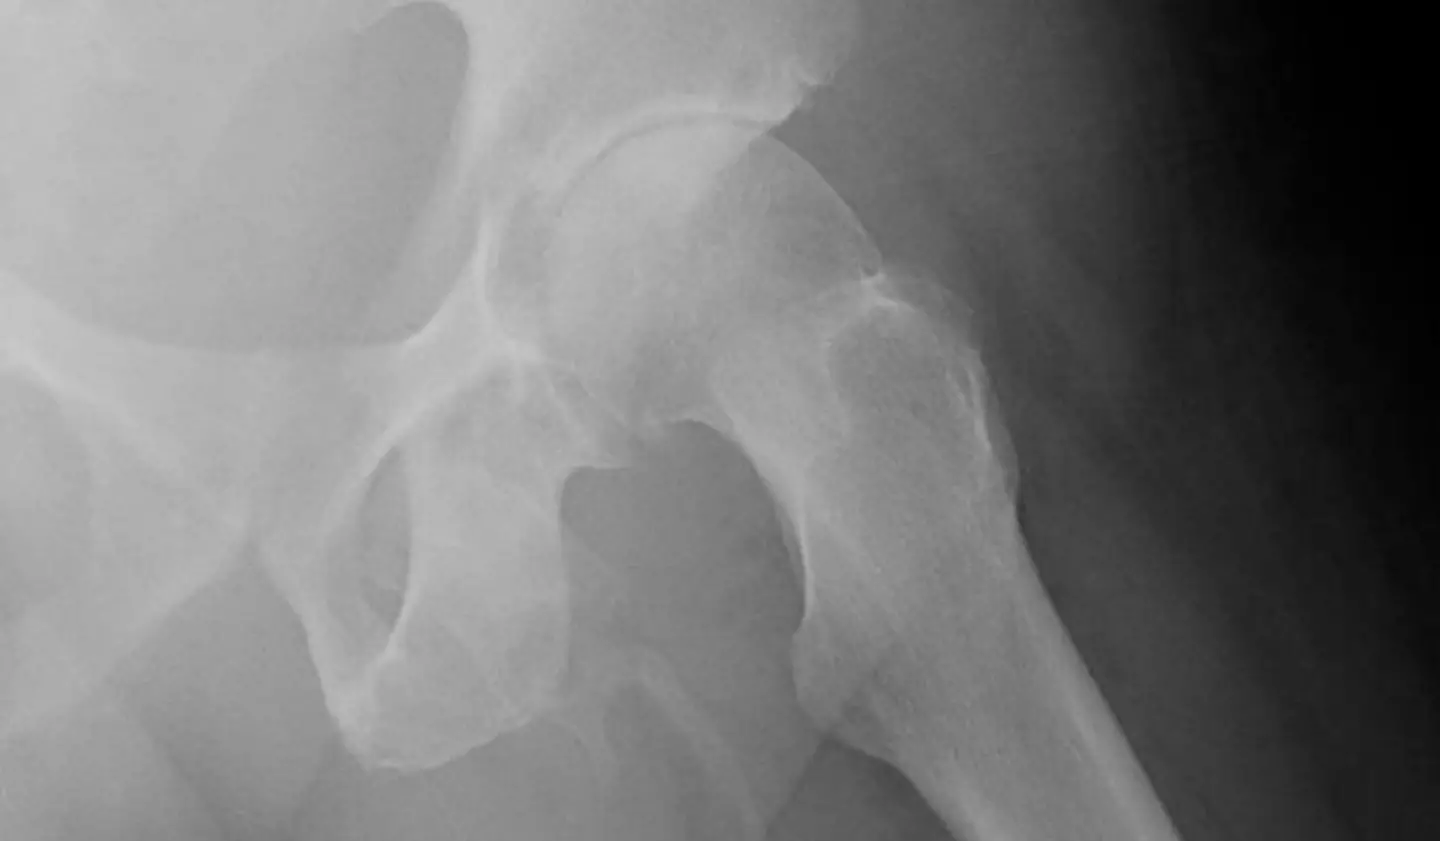

In the first x-ray, doctors were searching for fractures in the patient's hip area, which may be causing him pain in his left knee.

The medical expert describe it as an 'extensive, plaque-like calcification along the expected distribution of the penis', as calcium salts built up in the soft tissue along the shaft of his manhood, which was clearly seen in x-rays.